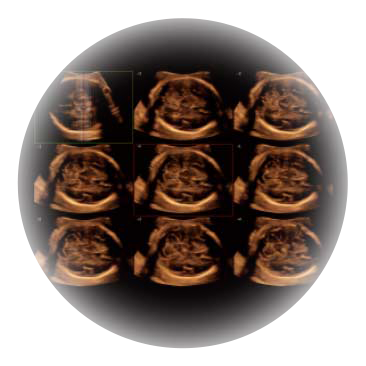

可同时显示组织结构表面和内部的轮廓信息,达到透视效果,为临床提供更丰富的诊断信息。

自动获取标准切面,自动完成测量,帮助医生快速完成检查,同时提升测量准确性。

宽频带腹部凸阵探头和腹部容积探头、大角度腔内探头和腔内容积探头、独特的生殖专用曲柄探头,为妇产应用提供全面诊疗方案。

卵泡结构的自动识别和测量,可显示多组测量数据。

大角度腔内容积探头,可完整包络子宫及盆底结构,充分展示组织结构毗邻关系。